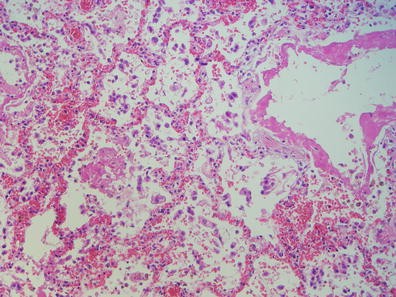

Objective: The aim of this study was to examine the clinicopathological features of succinate dehydrogenase subunit B (SDHB) mutation-related pheochromocytoma/paraganglioma (PCC/PGL).

Method: A total of 15 patients with SDHB-mutation were analyzed genomic DNA, clinical data on family history, catecholamine types, tumor metastasis, patient prognosis, and histology of the tumors. Histologic analyses were performed using the new classification named Grading of adrenal pheochromocytoma and paraganglioma (GAPP) classification that was made based on a nationwide Japanese survey. All tumors were scored from 0 to 10 points, and were also graded according to three differentiation types depending on the total score: well (0–2 points), moderate (3–6) and poor (7–10).